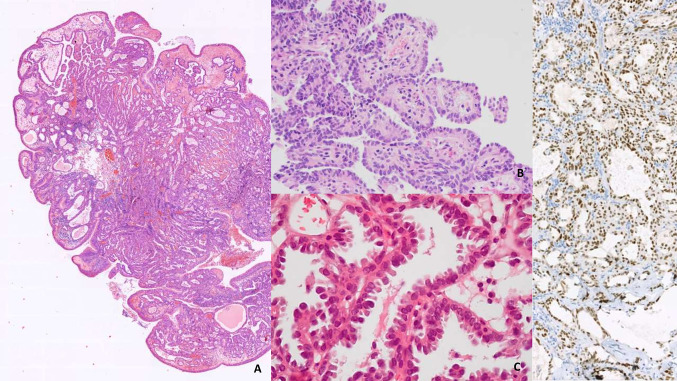

There are no significant differences between the two editions of the Blue Book in terms of histological description and classification of these carcinomas. Three subtypes are described: (i) non-keratinizing SCC (NK-NPC), (ii) keratinizing SCC (K-NPC) and (iii) basaloid SCC. Therefore, this article provides only a brief overview of the histologic subtypes that are described in detail in the WHO classification (Fig. 5).

Fig. 5.

Nasopharyngeal carcinoma. A, B Nasopharyngeal nonkeratinizing carcinoma: sheets of tumour with a squamous cell differentiation separated by a dense infiltrate of lymphocytes and plasma cells. C Subtype with glandular differentiation. D In situ hybridization with EBER probe

Nonkeratinizing SCC (NK-NPC) is the most common histologic subtype that may have some cytologic variations or lymphoepithelial features. Most of these tumors are related to EBV infection. Keratinizing SCC (K-NPC) does not differ from other keratinizing HNSCC in terms of histologic aspects. Basaloid SCC does not differ in histologic appearance from other locations.